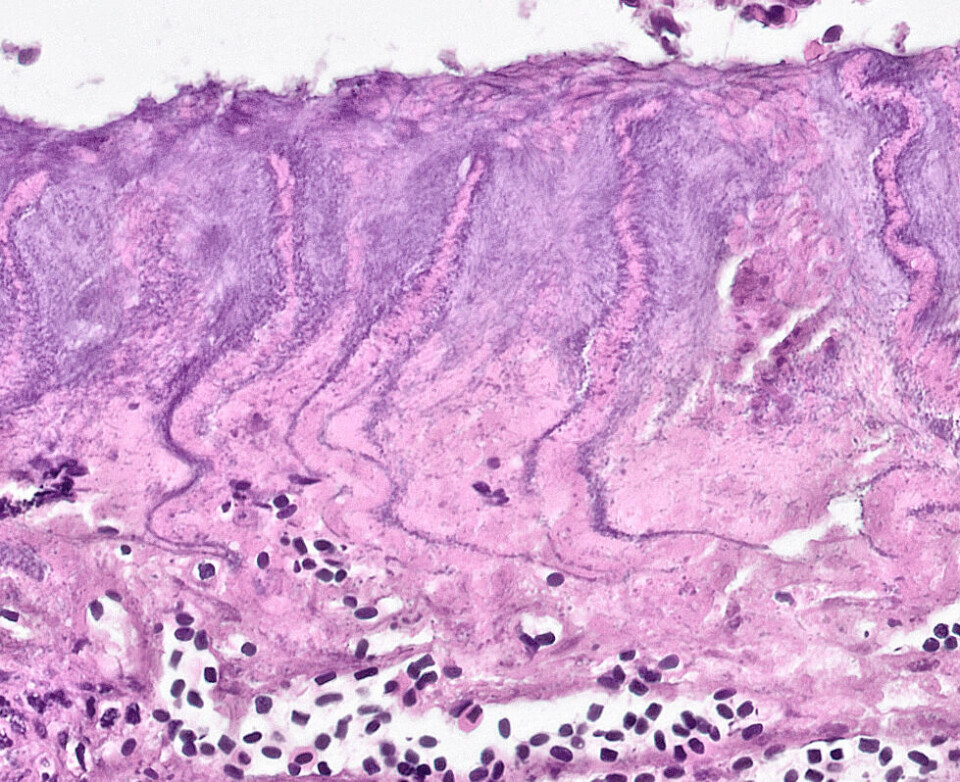

Tenacibaculum maritimum er ingen ny bakterie i Norge, men påvises nå på laks med et annet sykdomsbilde enn tradisjonell sårutvikling. Bakterien angriper først og fremst den ytre delen av gjellefilamentene og kan sees ved at man får et gult belegg på gjellene. Histologisk ser man at gjellene er nedbrutt ytterst på filamentene.

Nærbilde viser de filamentøse tynne trådformige bakteriene i det ødelagte gjellevevet.

Hvor mye bakterier man påviser ved PCR (CT-verdi) avgjøres i veldig stor grad om man tar ut prøvene fra slike områder med sår og gult belegg eller om man tar ut prøver fra andre gjellefilamenter. Histologisk ser man også forandringer i filamenter uten synlig påvisning av bakterien. Denne bakterien har evne til å skille ut enzymer og mulige toksiner som kan ha en påvirkning på hele gjellevevet, og ikke bare der bakterien har fått festet seg. Mye er derfor uklart om betydningen av denne bakterien på gjellehelsen generelt.